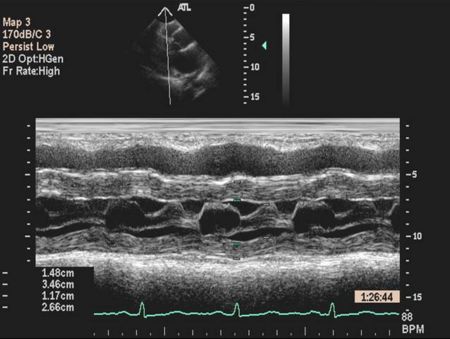

Ventricular M-mode

- Ventricular Wall Thickness

- Ventricular Chamber Size

- Intraventricular Masses